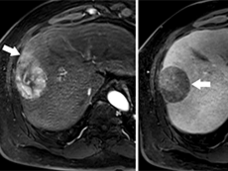

Nivolumab recibe aprobación acelerada de la FDA para cáncer avanzado de hígado

La FDA otorgó la aprobación acelerada del fármaco de inmunoterapia nivolumab (Opdivo®) para pacientes con cáncer avanzado de hígado y para pacientes que se trataron antes con la terapia dirigida sorafenib (Nexavar®).